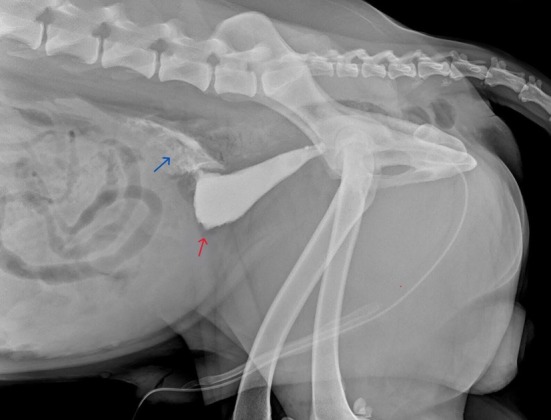

一只10岁雄性杂交犬出现呕吐和无尿。这只狗住在室内,主人没有报告任何创伤。超声检查和逆行尿道造影显示存在膀胱渗漏。行剖腹手术修复膀胱撕裂,同时行膀胱壁活检。组织病理特征为淋巴浆细胞性膀胱炎伴出血和肌层内多灶性纤维化区。自发性膀胱破裂无外伤证据是一个众所周知的,虽然罕见,条件在人类医学。在本病例中发现的慢性炎症,以及纤维化,导致膀胱壁变弱,导致穿孔。这是第一例有文献记载的继发于慢性炎症的自发性膀胱破裂的兽医病例,强调了将这种情况包括在无潜在创伤的尿腹膜患者的鉴别诊断中的重要性。

A 10-year-old male mixed-breed dog presented with vomiting and anuria. The dog was living indoors, and no trauma was reported by the owner. Ultrasonography and a retrograde urethrogram revealed the presence of a urinary bladder leakage. A celiotomy was performed to repair a urinary bladder tear, along with a biopsy of the urinary bladder wall. Histopathological features consisted of lymphoplasmacytic cystitis with haemorrhages and multifocal fibrotic areas within the muscular layers. Spontaneous rupture of the urinary bladder without evidence of trauma is a well-known, though rare, condition in human medicine. The chronic inflammation detected in the present case, along with fibrosis, caused the weakening of the urinary bladder wall, leading to perforation. This is the first documented veterinary case of spontaneous rupture of the urinary bladder secondary to chronic inflammation and highlights the importance of including this condition in the differential diagnosis of patients presenting with uroperitoneum without underlying trauma.